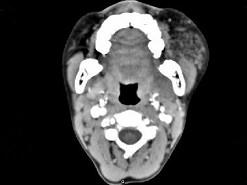

问题 男,12岁,左面颊肿大5年余,局部呈紫红色,CT如图所示,最可能诊断为 ( )

选项 A、慢性腮腺炎 B、下颌下腺慢性炎症 C、血管外皮瘤 D、动静脉畸形 E、蔓状血管瘤

答案 E